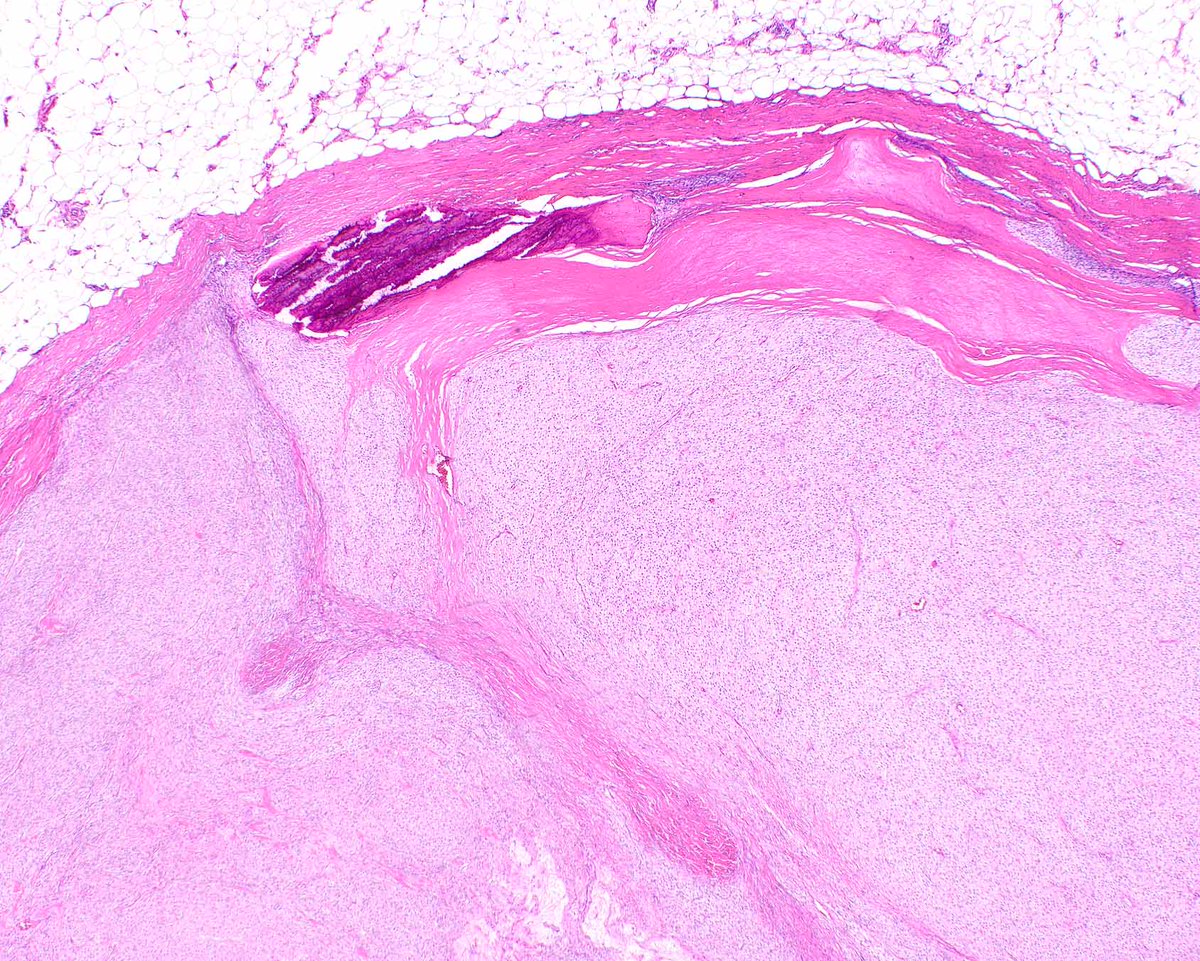

This classic example of ossifying fibromyxoid tumor displays a shell of bone and uniform cytologic features; it's an H&E diagnosis. Without classic features, detecting PFH1 rearrangements (several partner genes reported) is useful. #UMiamiPath PMIDs: PMID: 2476942, 23887158.